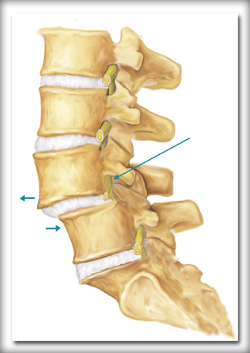

The spine is made of series of connected bones called as vertebrae. Spondylolisthesis is abnormal forward displacement of one vertebra over the other which occurs mainly in low back region. Spondylolisthesis occuring in young age may be due to abnormal development ( Dysplastic spondylolisthesis) or due to fractute in the connecting bone( Lytic spondylolisthesis). In old age degeneration is the main cause of spondylolisthesis(Degenerative spondylolisthesis).

Patient usually presents with low back pain related to activities . It may be associated with leg pain if there is nerve compression.

Xray is the first line of investigation. MRI might be needed if the pain is persisting or if nerve compression is suspected.

Most of the patients settles down with physiotherapy- mainly back exercises , pain medications and activity modification. If the pain is severe and persisting surgical intervention may be indicated. Commonly done surgery is Lumbar decompression and pedicle screw fixation.